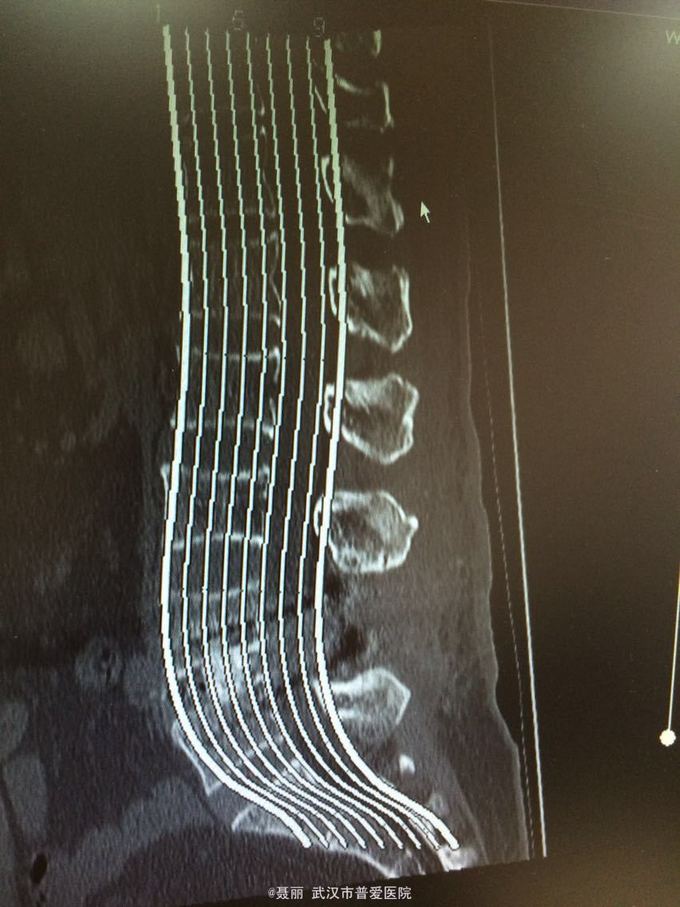

患者,女,61岁 因腰部疼痛,伴左下肢酸胀、疼痛、麻木5月余入院。 患者约5月前无明显外伤等诱因感腰腿疼痛不适,以腰部及左下肢为主,活动后左下肢疼痛加重,休息可缓解。 既往病史:既往体健,否认高血压、糖尿病等其他传染病史,否认食物药物过敏史。

辅助检查:2015年2月27号到我院拍腰椎MRI检查提示:L4椎体Ⅰ-Ⅱ度滑脱,腰椎退变。

初步诊断:腰椎滑脱症 治疗计划:1、完善相关检查:胸片、心电图,血常规,尿常规,肝肾功能电解质、术前全套 2,活血化瘀扩管治疗。卧床休息。 L4滑脱复位+L4/5椎间盘摘除、椎管减压+椎间cage3植骨融合术